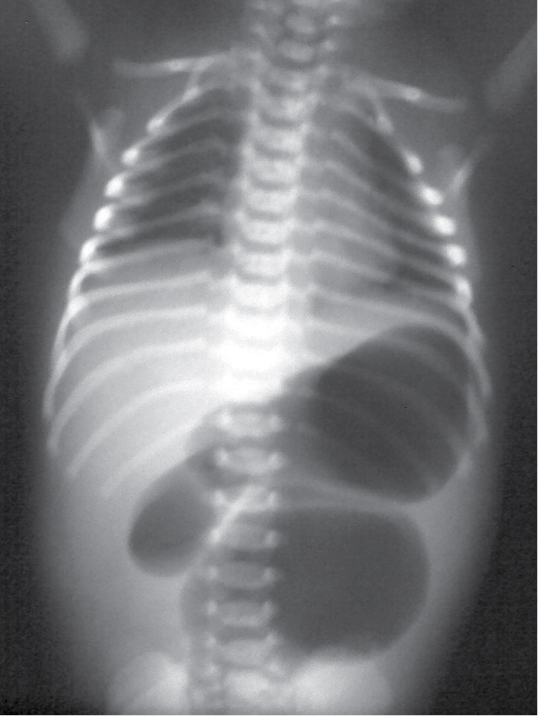

A preterm baby boy of 34 weeks gestation was

born via normal delivery. There was history of polyhydramnios and the antenatal

ultrasonography finding was suggestive of upper gut obstruction. Baby weighed

1.9 kg. Abdomen was soft without any distension. Blood reports were

normal. Abdominal X-ray revealed three prominent gas shadows in upper abdomen with gasless distal abdomen.